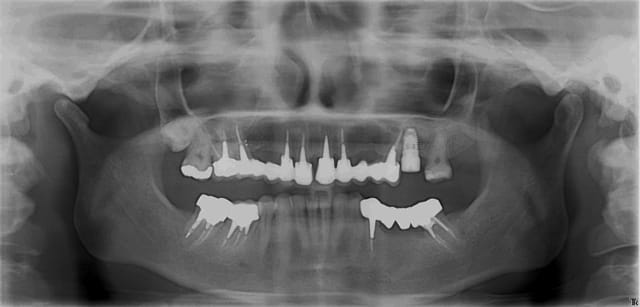

Patiente porteuse d'un bridge de + 10 ans réalisé par un confrère. Celui-ci ayant quitté la région, je la suis depuis peu.

Le bridge est pas trop mal, aucune raison de le déposer pour le moment. La patiente ne le souhaite pas pour le moment, malgrès un esthétisme améliorable. Maintenance parodontal bien suivit.

J'ai dût extraire 26 (carie+++ sous une couronne unitaire)

J'ai réalisé une fenêtre aux niveau des "apex" de 26 pour soulever la membrane et mettre du biomat.

Implant et vis de cica dans la foulée (couple >à 50N obtenue sous forant) (Nobel Replace Speedy WP 5*10mm)

Question: pourquoi à l'OPT l'implant parait toujours plus mésial ?

ps: le polype à droite (asymptômatique) semble venir de la 18 qui est complétement dans le sinus (au scan) ou de 16 mais les canaux semblent obturés à l'apex